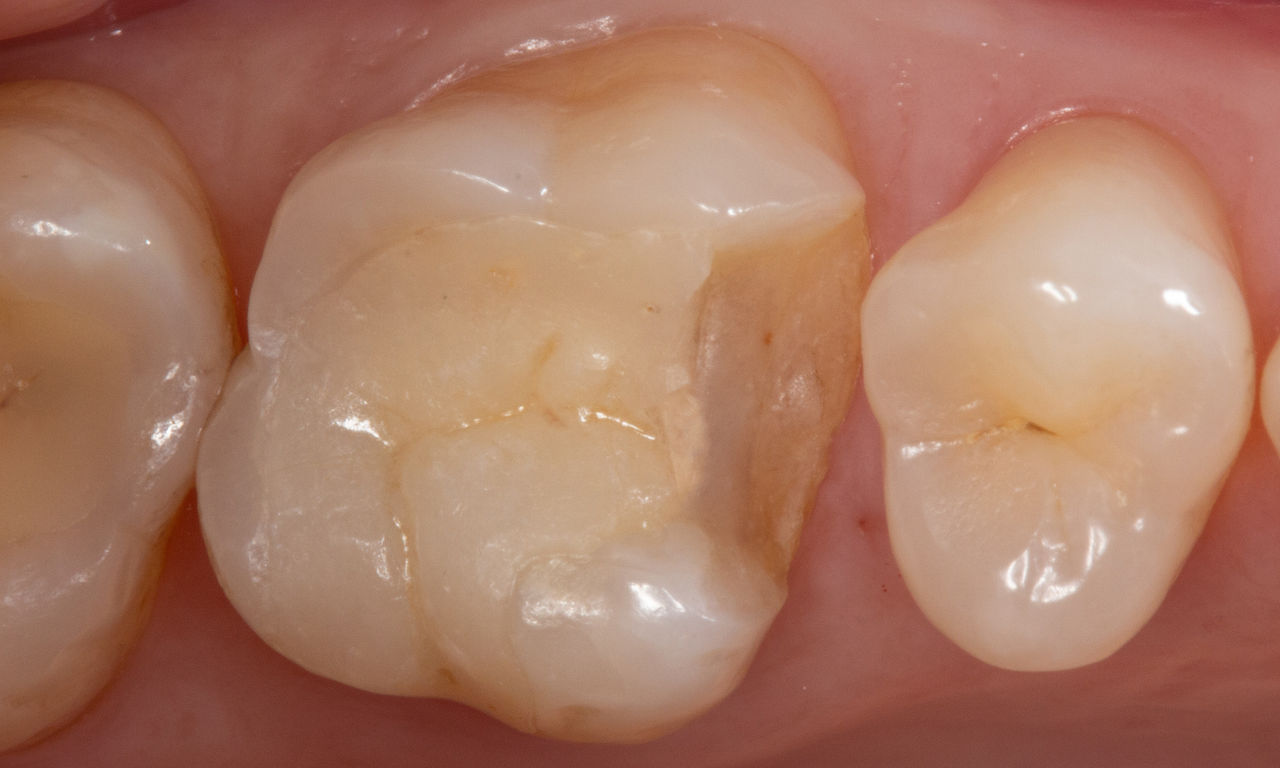

A lower second molar with sensitivity presented with cracks as well as an extensive Class I composite restoration on the buccal surface. According to the minimally invasive concept a CAD/CAM partial crown was planned, fabricated and bonded using CEREC Tessera in a single visit.

Before: Failed amalgam restoration needing replacement. Patient complaining of sensitivity and tooth presenting multiple cracks.

After: Chairside CAD/CAM partial crown restoration fabricated with CEREC Tessera Advanced Lithium-Disilicate glass ceramic.